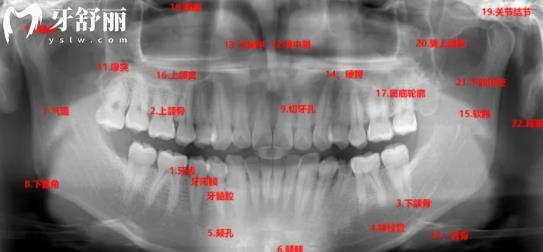

牙科中比较常见的牙片种类一般有小牙片、全景片和侧位片等,其中能够直观看到牙齿问题更多的就是口腔全景片。

口腔全景片中可以拍到全部的牙齿、牙龈牙周以及上下颌骨到鼻腔的位置。因此可以由全景片诊断出关于蛀牙、智齿、牙槽骨是否被吸收等情况。也就是说在拔智齿、做牙齿矫正和种植牙等牙科项目前是必须要拍的。